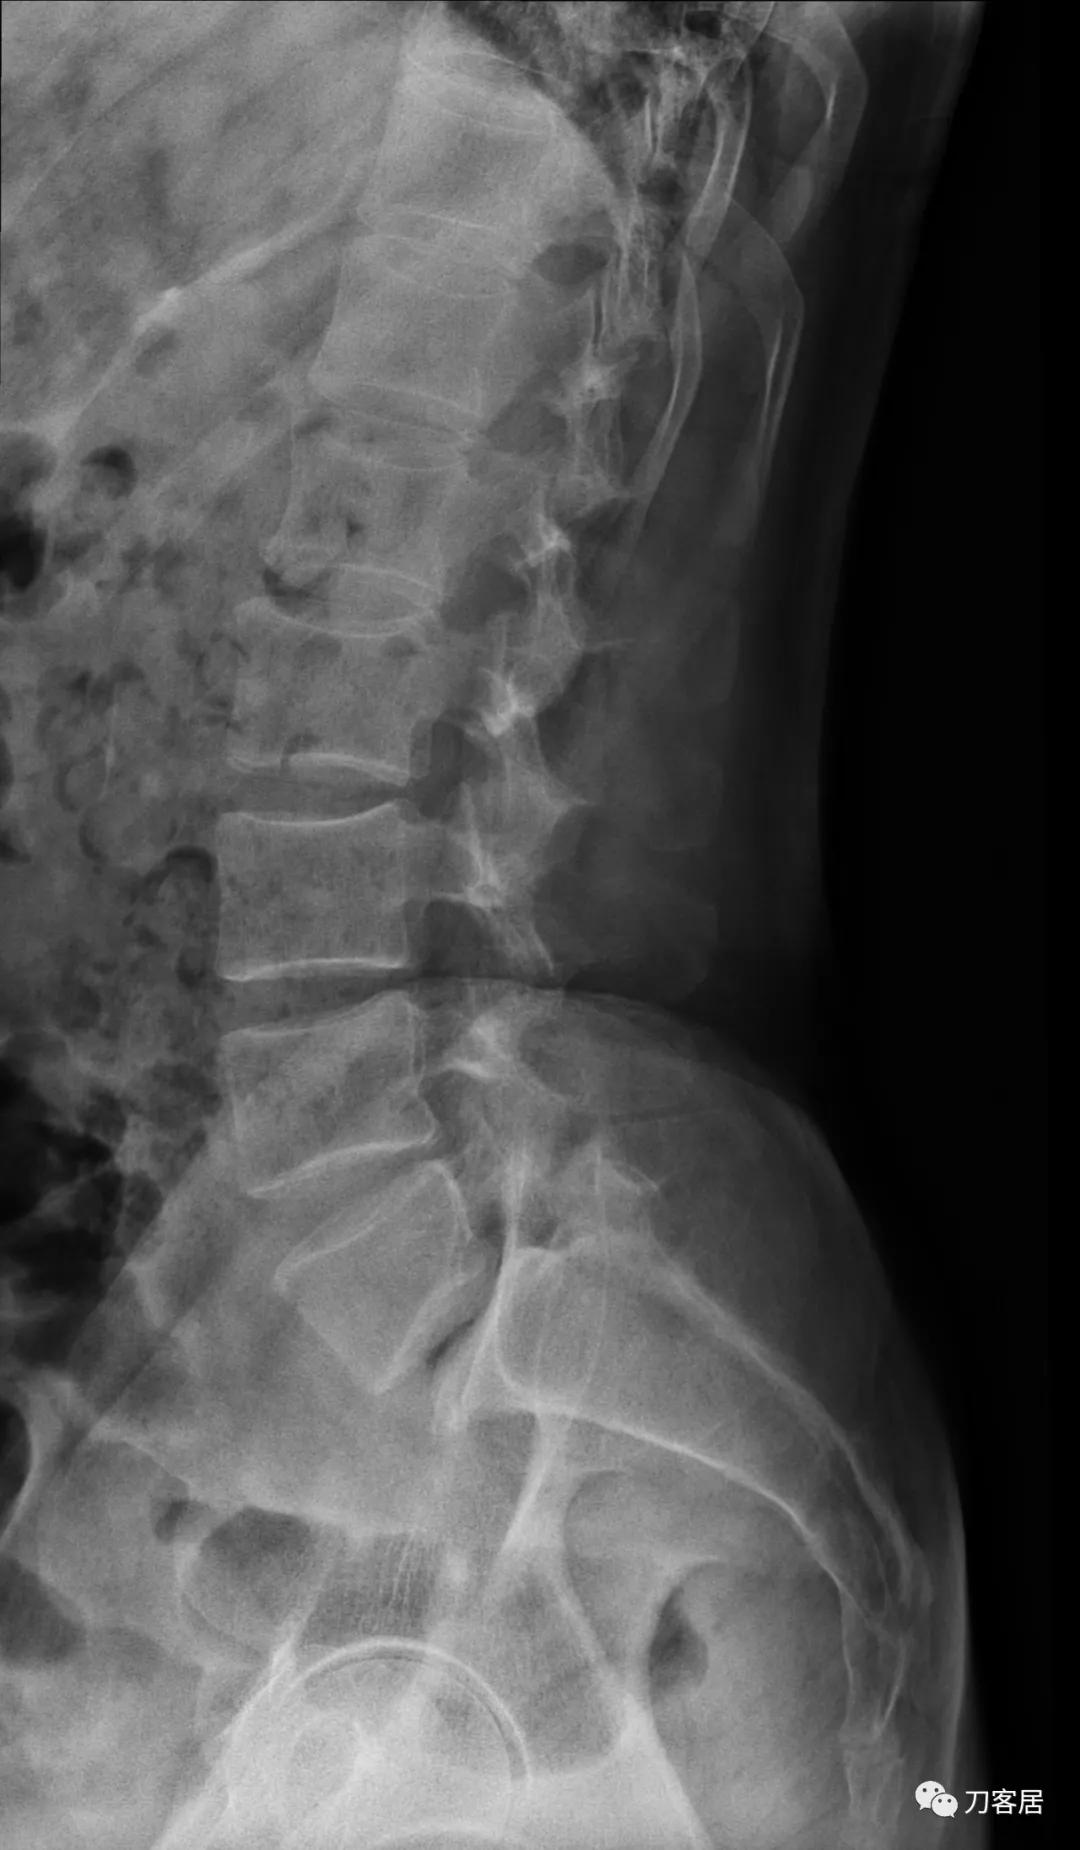

自带影像学检查提示腰5椎体前滑脱,腰5峡部裂,椎管狭窄不严重。

诊断:腰5峡部裂,腰5椎体前滑脱1度,骨质疏松症。

图4. 20210616术前腰椎侧位X线片